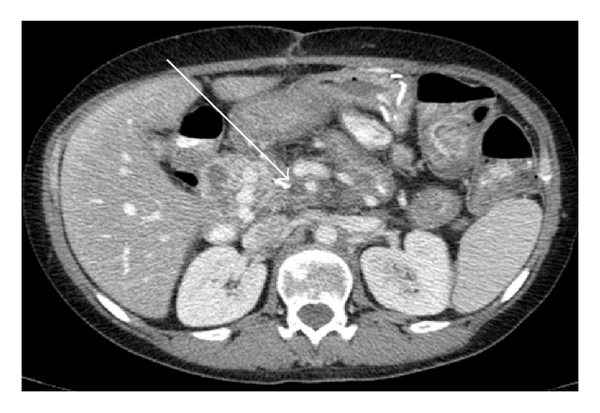

As Figures 1–5 demonstrate, the immediate postablation bed and zone are invariably larger than the original ablated tumor. We remain descriptive because the entire bed was extremely difficult to measure owing to the amorphous, irregular nature of the ablation. Moreover, the ablated tissue is not within an encapsulated organ; therefore, the ablation zone does not have defined borders as seen after, for instance, liver ablation. Four patients that showed continued stable disease are highlighted in Figures 1 through 4. An amorphous, hypoattenuating region with irregular shape persisted in subsequent CT scans in all patients with “stable disease.” Moreover, the ablation zone was typically smaller (due to decreased edema, hyperemia, and granulation tissue) than the immediate postablation bed in the following months and remained stable provided there was no recurrence. Imaging findings demonstrating recurrence are shown in Figure 5. Along with persistent irregular shape the ablation zone showed increased tumor bulk and extension as well as new mass effect (new narrowing of a blood vessel). Enhancement of the ablative bed was variable and often showed increased enhancement in the three-month and longer follow-up images. This was felt to be related to development of granulation tissue and fibrosis.

In our study, we found that the postablation bed is larger in volume than the initial mass. This is expected because it contains the tumor and the ablative margin. The postablation bed and zone appear irregular, amorphous, and hazy without margins or true boundaries. The ablation zone may decrease in size from the initial post-op bed to the initial surveillance study as the surrounding edema/fluid and inflammation resolve revealing the true ablation zone; however, as mentioned above, since there have been reports of an ongoing apoptotic process that persists up to 6–8 weeks after ablation, it will not be unusual to see some increase in volume in surveillance [19, 20]. Therefore, size is considered secondary in the CT evaluation for this reason and because the postablative bed/zone has poorly defined margins, making objective imaging assessment (size, attenuation) cumbersome. This may undoubtedly affect the accuracy and reproducibility of the measurement. Nonetheless, any increase in volume after stabilization of the postablation zone is considered worrisome for recurrence (Figure 5).